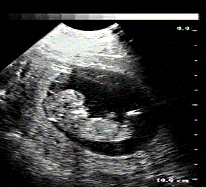

Ультразвуковая

эхография (эхография, эхолокация, ультразвуковое сканирование, сонография, УЗИ)

(Рис. Рис.) базируется на акустических высокочастотных колебаниях от 2 x

104 до 108 Гц, которые уже не воспринимаются человеческим ухом. Ультразвук

хорошо распространяется по тканям организма даже при низких уровнях энергии

(0,005-0,008 Вт/см2), которые в сотни и тысячи раз меньше доз,

используемых при терапевтических воздействиях. Отраженные ультразвуковые

сигналы улавливаются, трансформируются и передаются на воспроизводящее устройство

(осциллоскоп), с которого и воспринимаются эти сигналы. Применение эхографии в

кардиологии позволяет определить наличие и характер порока сердца,

обызвествление створок клапанов при ревматическом пороке, выявить опухоль

сердца и другие его изменения. При диффузных поражениях печени эхография

позволяет различить цирроз, гепатит, жировую дистрофию, определить расширенную

и извитую воротную вену.

Рис. Проведение УЗ-исследования.

Эхографическое

исследование селезенки позволяет установить ее расположение, выявить увеличение

(что может быть одним из косвенных признаков цирроза печени), изучить структуру

этого органа. Метод ультразвуковой эхографии используется в неврологии

(исследование головного мозга, величины отслойки сетчатки, определение

локализации и размеров инородных тел, диагностика опухолей глаза и глазницы), в

оториноларингологии (дифференциальная диагностика причин поражения слуха и

др.), в акушерстве и гинекологии (определение сроков беременности, многоплодной

и внематочной беременности, диагностика новообразований женских половых

органов, пио - и гидросальпикса, исследование молочных желез и др.), в урологии

(исследование мочевого пузыря, предстательной железы). В настоящее время под

контролем эхографии выполняют прицельную биопсию внутренних органов -

щитовидной железы, печени, почек и др., извлекают с помощью специальных

пункционных игл содержимое кист, абсцессов печени, поджелудочной железы и др.,

при наличии специальных показаний вводят растворы антибиотиков непосредственно

в желчный пузырь при обострении холецистита или в полость нагноившихся кист

печени, поджелудочной железы и др., проводят и другие диагностические и

лечебные манипуляции.

Рис. Ультразвуковое исследование (УЗИ)